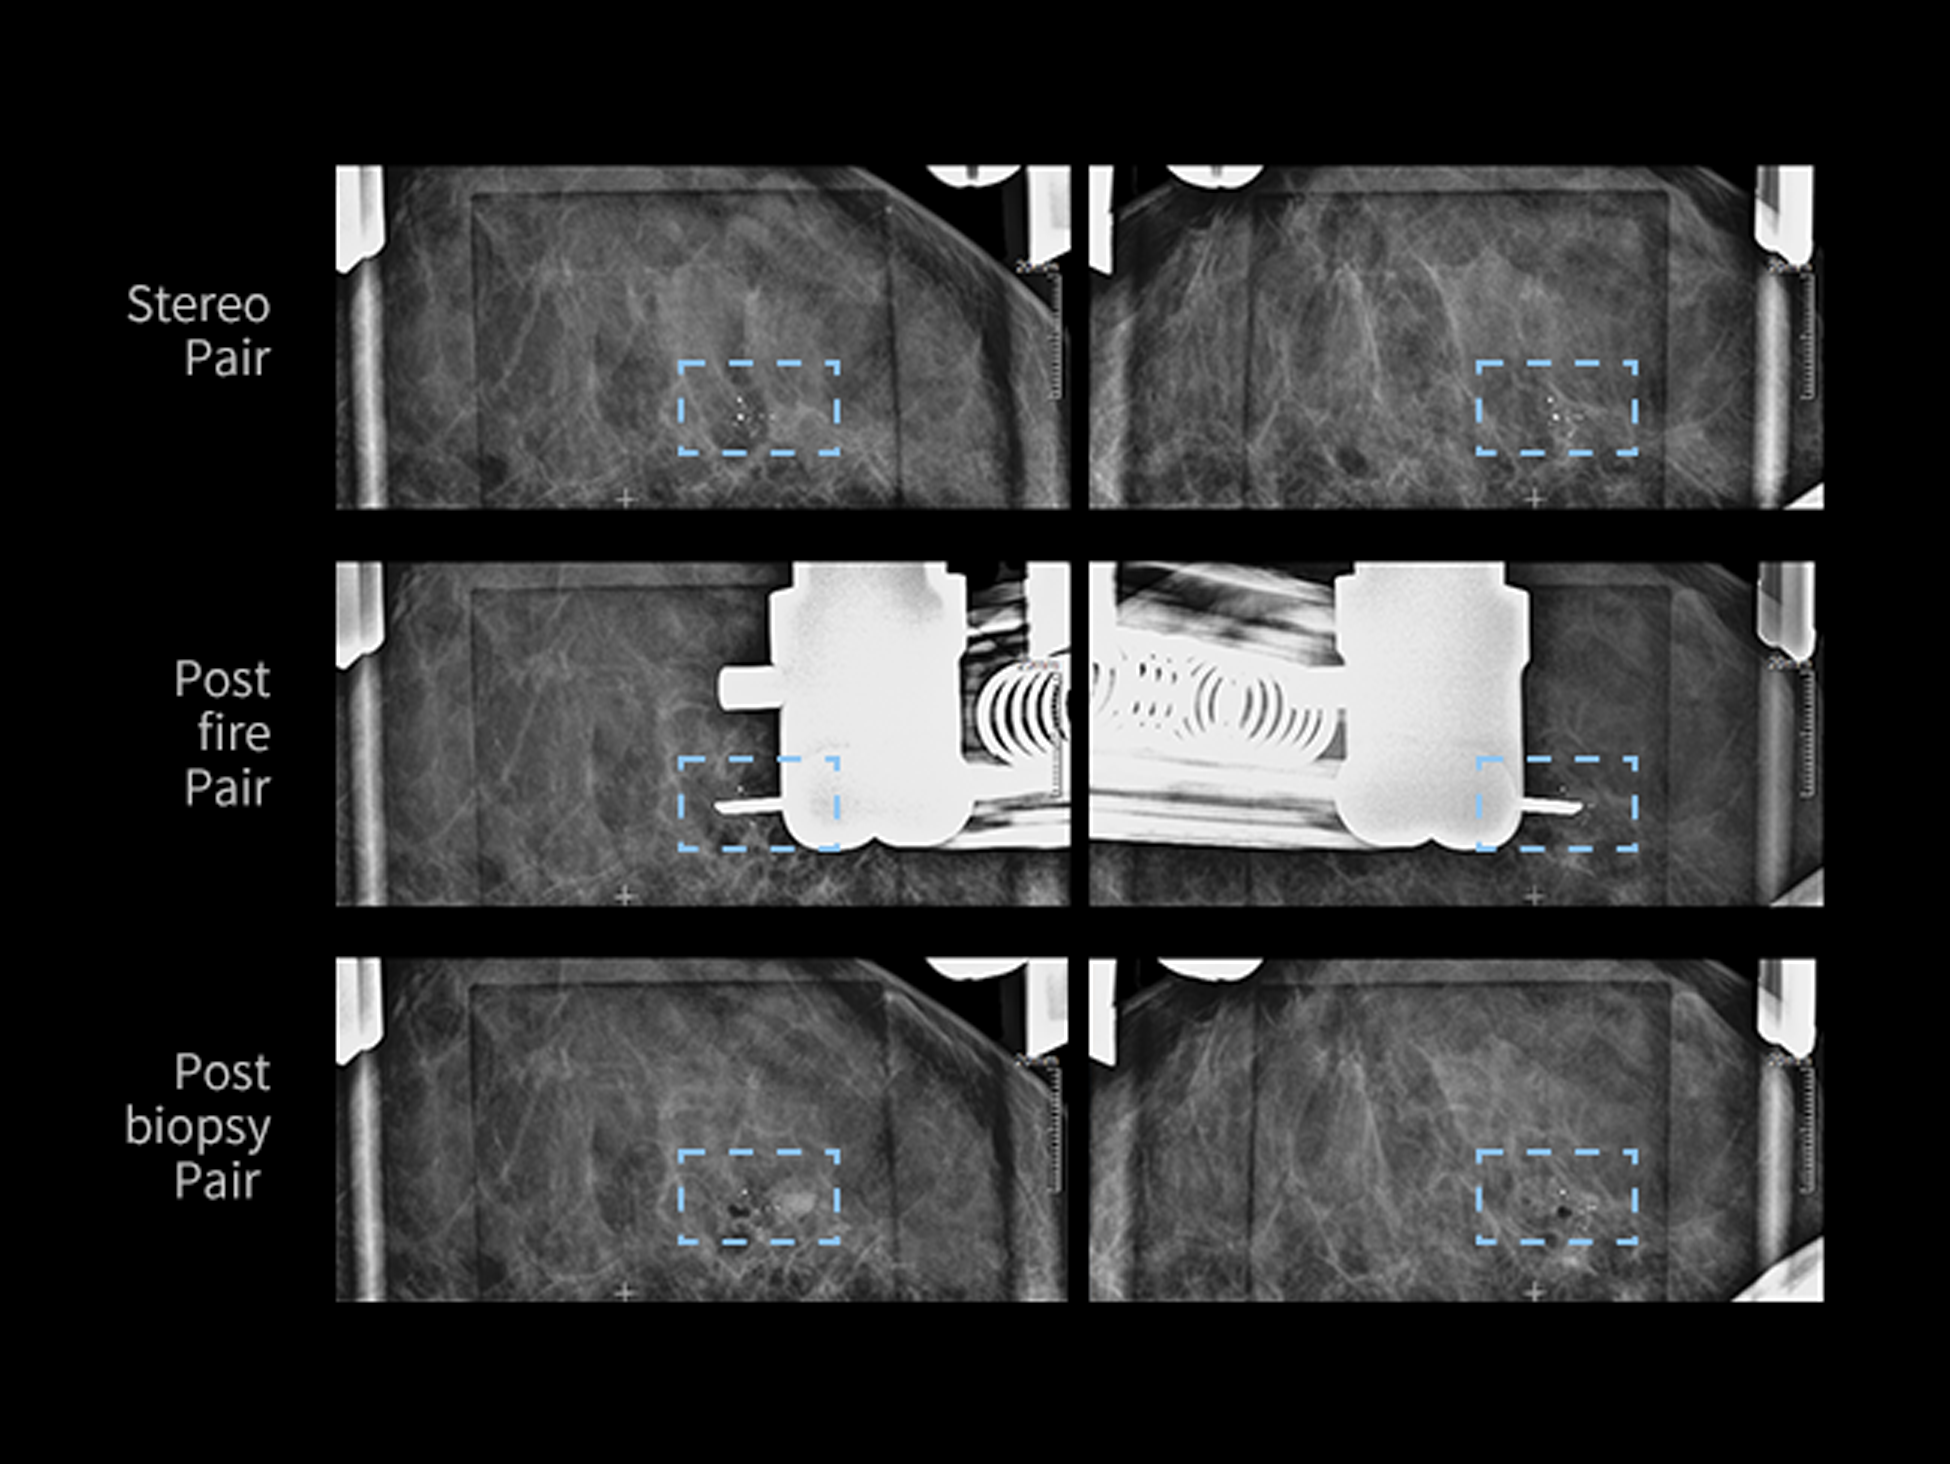

Biopsie

Funcția sincronizează mișcarea dintre tubul de raze X și detectorul plan, reducând semnificativ timpul de poziționare. Mecanismele de siguranță integrate protejează atât operatorul, cât și pacientul.

| Acuratețea țintei biopsiei | ±1 mm |

| Domeniu de mișcare | X: 60 mm ±1 mm Y: 50 mm ±1 mm Z: 110 mm ±1 mm |

| Direcție biopsie | Orizontală / Verticală |

| Ghid ac | 12G, 13G*, 14G, 15G*, 16G, 18G, 19G, 20G |